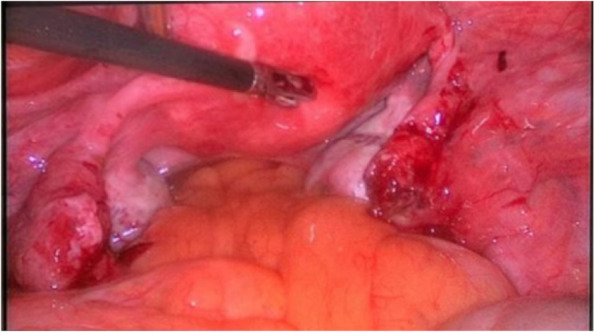

Fig. 2.

Bilateral tubal ectopic pregnancies (a) and a small amount of blood (b) in the cul-de-sac are seen